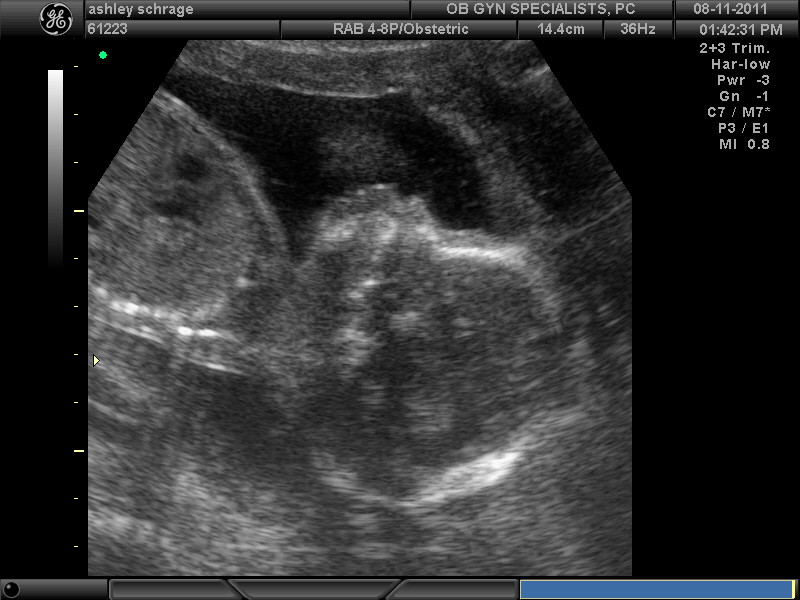

I already love this little man so much my heart aches in a way it never has before.

I'm so excited for you and Travis and also Grandma! Nice ultra sound photo, he's adorable!